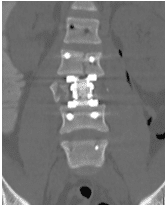

Un chico de 18 años se cayó desde tres pisos. Pérdida casi total de todas las funciones neurológicas por debajo del nivel de lesión con afectación casi total del intestino y la vejiga

Cirugía

El paciente fue operado y el conducto espinal limpiado de todos los fragmentos óseos. La columna vertebral se fijó de lado y la parte trasera para eliminar la inestabilidad.